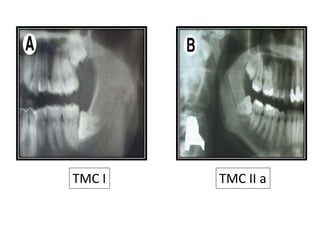

TMC I Roots of the third molar above the

mandibular canal

TMC IIa Mandibular third molar roots are in

relation to the mandibular canal

TMC IIb More than a third of the molar roots

are in relation to the mandibular

canal

TMC III All third molars roots are localized

below the mandibular canal

TMC I TMC II a

TMC IIITMC IIb